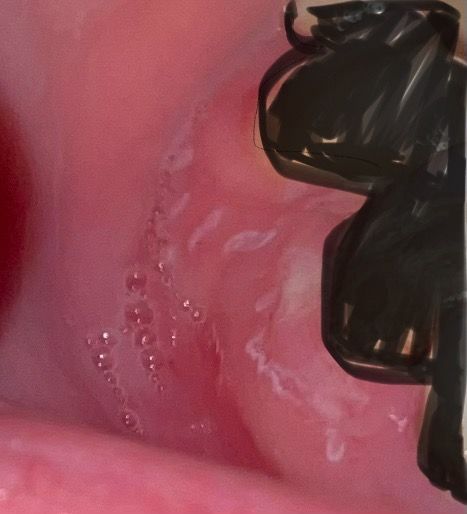

구강 안에 흰색 물집이헤르페스인가요??

하루 전부터 갑자기 구내염처럼 저렇게 흰색 물집이 생겼습니다 (거품같이 보이는 것은 침입니다..)

남자친구랑 구강성교 바로 다음 날 갑자기 저렇게 흰색 물집이 생겼는데 구강 헤르페스에 감염된 건가요? 그 이전에는 한 번도 입술에 뭐가 나거나 했던 적이 없습니다. 지금도 입술 주변에는 물집이 생기지 않았고 성기 역시 발생하지 않았습니다

• 1번 째 사진